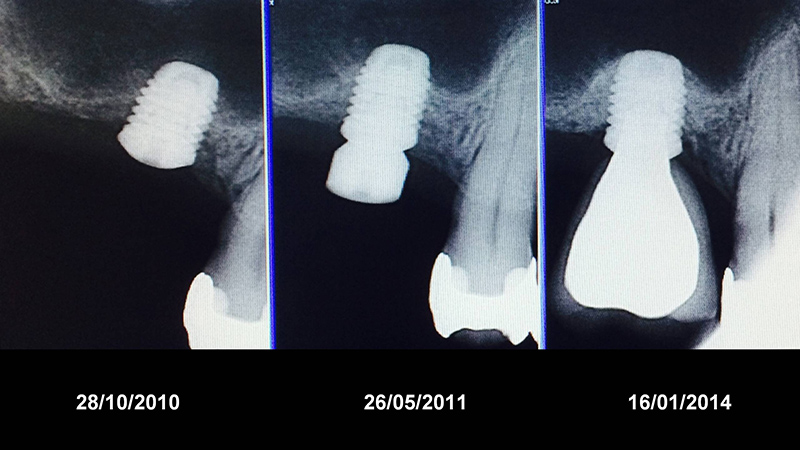

Évolution radiologique d’un environnement osseux péri-implantaire après un protocole d’extraction puis implantation.

En 2010, Esposito et d’autres ont montré que l’abord crestal est abordable à partir de 3-4 mm.

Évolution radiologique d’un environnement osseux péri-implantaire après un protocole d’extraction, puis implantation/comblement sinusien. Notez le gain osseux après seulement 6 mois.

Le même cas 3 ans après, avec couronne mise en place.

Pose d’un implant de 7 mm, puis évolution de l’os périmplantaire apicale au fil des années.

10 ans après, notez l’aspect radiologique de la corticale péri-implantaire.